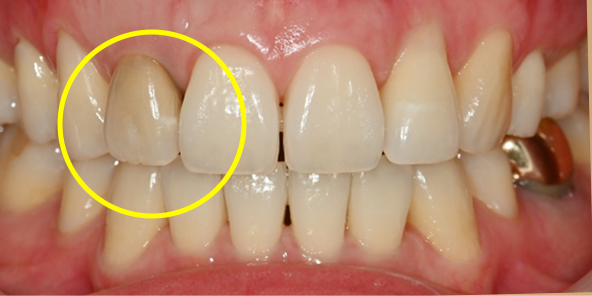

치료 전

임플란트 최종 결과

BEFORE/AFTER

BEFORE

AFTER